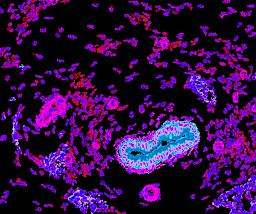

Pancreatic ductal adenocarcinoma is a lethal disease with limited treatment options and poor survival. We studied 83 spatial samples from 31 patients (11 treatment-naïve and 20 treated) using single-cell/nucleus RNA sequencing, bulk-proteogenomics, spatial transcriptomics and cellular imaging. Subpopulations of tumor cells exhibited signatures of proliferation, KRAS signaling, cell stress and epithelial-to-mesenchymal transition. Mapping mutations and copy number events distinguished tumor populations from normal and transitional cells, including acinar-to-ductal metaplasia and pancreatic intraepithelial neoplasia. Pathology-assisted deconvolution of spatial transcriptomic data identified tumor and transitional subpopulations with distinct histological features. We showed coordinated expression of TIGIT in exhausted and regulatory T cells and Nectin in tumor cells. Chemo-resistant samples contain a threefold enrichment of inflammatory cancer-associated fibroblasts that upregulate metallothioneins. Our study reveals a deeper understanding of the intricate substructure of pancreatic ductal adenocarcinoma tumors that could help improve therapy for patients with this disease.